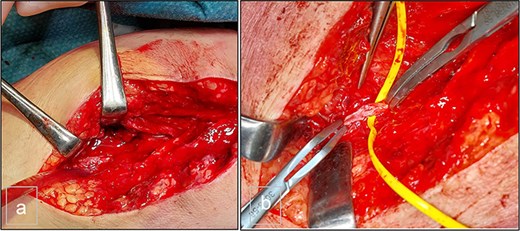

The patient was a 55-year-old female who was admitted to the Surgery Department due to recurrent bleeding and swelling at the surgical site following the removal of elective osteosynthesis material from the left tibia and patella by orthopedic surgeons. Initial investigation involved Doppler ultrasonography of the left leg, which revealed a large hematoma within the deep muscle structures of the proximal and middle thirds of the calf. An anechogenic pocket, exhibiting arterial flow on Doppler-color imaging, was identified, consistent with a pseudoaneurysm with dimensions of 28 × 20 × 24 mm, and it was supplied by arterial flow from the posterior tibial artery (PTA). The PTA remained patent distally but demonstrated a demodulated, monophasic flow with a velocity of 12 cm/s (Fig. 1).

Preoperative duplex sonography. (a) M-mode. Pseudoaneurysm of the posterior tibial artery (vascularized anechogenic pocket). (b) Doppler mode and (c) Doppler mode. Identification of communication with the medial wall of the PTA.